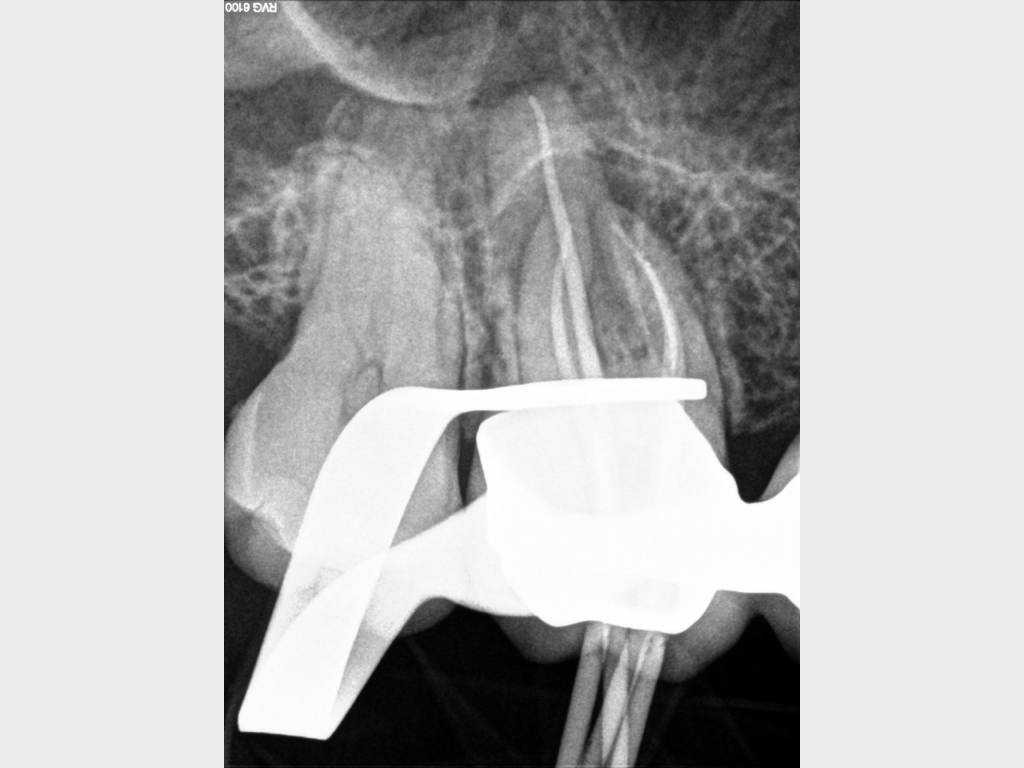

Heilung Express oder Radiodontics